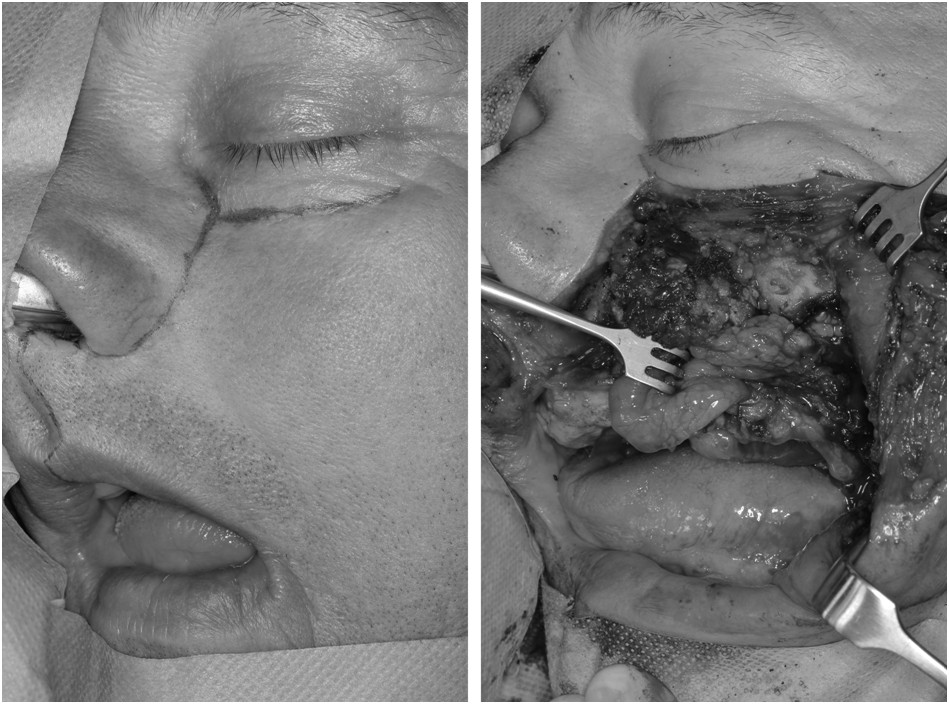

Pacjentka w wieku 72 lat podaje, że 5-6 lat wcześniej pojawiło jej się wygórowanie w okolicy nosa, podkrwawiające okresowo przez kilka dni, a następnie tworzy się strup. Nie daje dolegliwości bólowych. W tym czasie osiągnęło średnicę ok. 1 cm w okolicy kąta oka i drugie 2 mm na grzbiecie nosa. Ponadto pacjentka podaje, że choruje na nadciśnienie tętnicze, chorobę niedokrwienną serca i cukrzycę, 2 lata temu z powodów zawrotów głowy przewróciła się doznając urazu twarzy. Wskaż prawidłowe rozpoznanie kliniczne dotyczące obrazu na fotografii pacjentki: